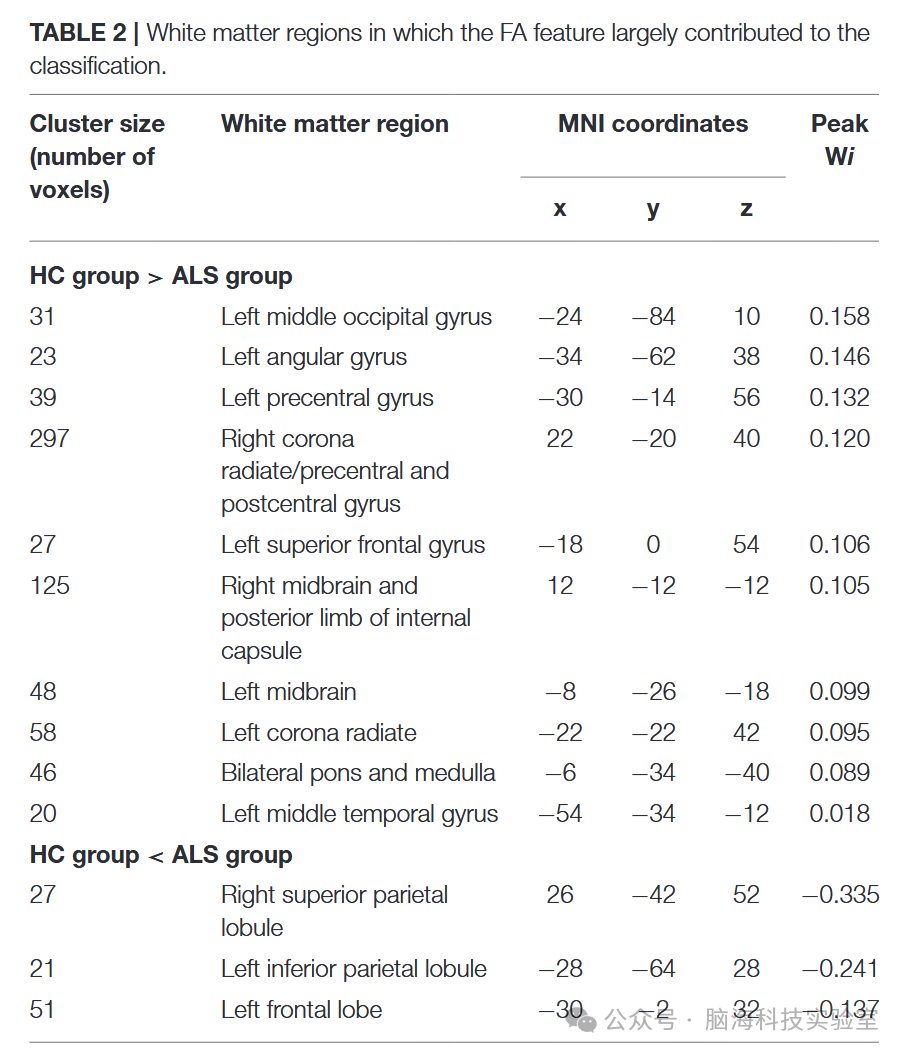

表2

权重向量 w 用于指示两组之间最具区分能力的特征子集。因此,通过设定阈值为最大权重向量分数的≥10%,识别出对区分贡献最大的白质(WM)区域的FA值。表2 列出了这些区域的详细信息,并根据它们对组间区分的贡献(即权重向量 w)对这些区域进行了排序。图7 展示了 SVM 分析生成的属性权重的相关分布。在健康对照组(HC)中,FA值相对较高的白质区域位于多个部位,例如双侧放射冠和中央前回、右侧中央后回、右侧内囊后肢、左侧额上回、左侧角回、左侧颞中回、左侧枕中回、双侧中脑以及双侧桥脑和延髓;而在患者组中,FA值相对较高的白质区域位于左侧额叶、左侧缘上回和右侧缘上回。

图7

与以往的研究一致,研究发现ALS中FA降低的白质区域涉及双侧中央前回和皮质脊髓束(CST)通路,例如双侧放射冠、右侧内囊后部、双侧中脑、双侧桥脑和延髓。中央前回是初级运动皮层(PMC)的一部分。已有研究表明,ALS中PMC出现退行性变化,例如Betz细胞显著减少和皮层变薄。皮质脊髓束(CST)连接运动皮层和脊髓中的神经元,是与皮层对脊髓活动控制相关的纤维。CST的退行性变也是ALS的一个标志。总之,这些与运动相关的区域受损可能导致运动神经元功能障碍,并引发ALS患者所表现出的相关症状(例如,肌肉无力和自主控制能力丧失)。

FA降低的区域还包括一些非运动区域,例如右侧中央后回、涉及左侧额上回、左侧角回和左侧颞中回的左侧上纵束(SLF),以及涉及左侧颞中回和左侧枕中回的左侧下纵束(ILF),这与以往研究的结果一致。例如,已有研究表明,ALS中中央后回显著的皮层变薄,即初级体感皮层,与疾病的严重程度相关。此外,上纵束(SLF)连接额叶、顶叶和颞叶,并在语言功能中发挥关键作用,在ALS中受到破坏。同时,左侧下纵束(ILF)的损伤——该纤维主要与视觉处理、语言/语义功能以及情绪调节相关——已在ALS患者中被报道。因此,这些在非运动区域出现的损伤(表现为 FA 值降低)可能与 ALS 中报告的各种非运动功能障碍相关,例如感觉障碍、语言功能障碍,以及行为和精神异常。

相比之下,研究的结果显示ALS患者的多个大脑区域,包括左额叶、左顶下叶和右上顶叶的FA相对增加。推测这些变化可能与ALS的功能补偿或脑结构重组有关。与这一猜测一致,ALS中已经证明了几种补偿现象,如灰质体积增加或特定大脑区域过度激活所反映的那样。

在优化后的SVM模型中,FA值对分类贡献最大的白质区域主要涉及运动和非运动区域,包括双侧冠状辐射、中央前回、右侧后中央回、右侧内囊后肢、左侧额上回、左侧角回、左侧中颞回、左侧中枕回、双侧中脑、双侧脑桥和延髓。相比之下,ALS患者中FA值相对较高的区域包括左侧额叶、左侧角回和右侧顶上小叶。